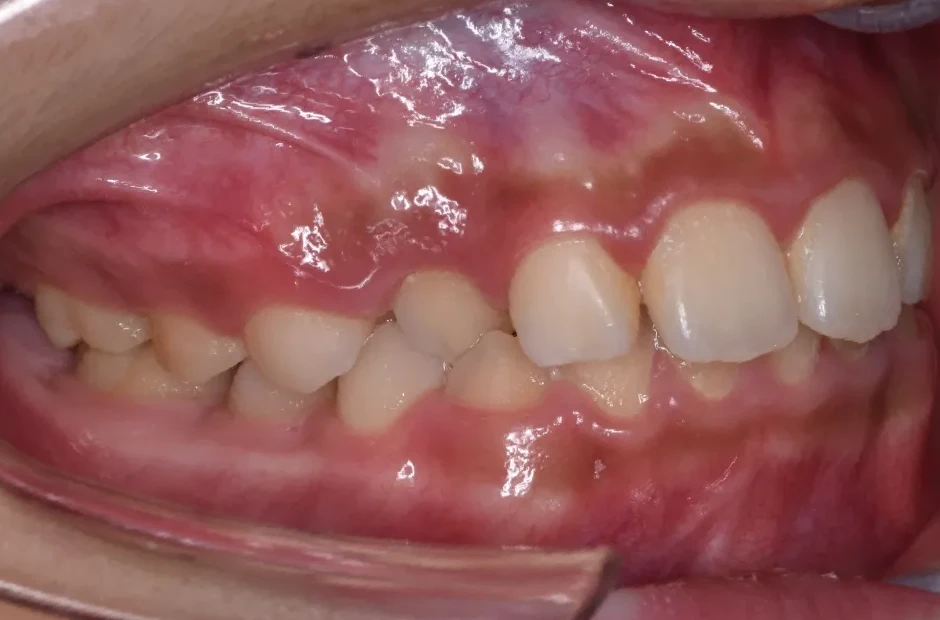

前歯部反対咬合

| 診断名・主訴 | 前歯部反対咬合 |

|---|---|

| 年齢・性別 | 14歳・男性 |

| 治療期間・回数 | 1年2か月 |

| 治療に用いた主な装置 | ブラケット矯正 |

| 抜歯部位 | なし |

| 治療費 | 60万円(税抜) |

| リスク・副作用 | 装置による違和感・疼痛・歯肉退縮・歯根吸収・虫歯のリスクなど |

治療前

治療後